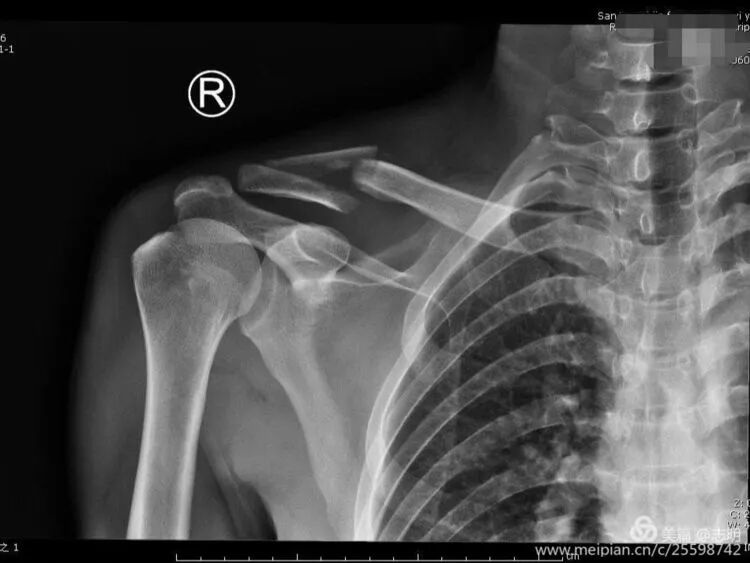

Temporary Fixation:

Once an acceptable reduction is achieved, maintain it with temporary percutaneous K-wires. As noted in the original text, "对于长斜形等易临时固定的骨折,可经皮钻入1.5mm克氏针维持复位" (For long oblique fractures and others easily temporarily fixed, 1.5mm Kirschner wires can be percutaneously drilled to maintain reduction). Ensure K-wires do not interfere with subsequent plate placement.

(Fluoroscopy showing K-wire stabilization).

Once a satisfactory reduction is achieved, it must be temporarily secured prior to plate application. Percutaneous Kirschner wires (K-wires) are commonly used for this purpose. The seed content states: "对于长斜形等易临时固定的骨折,可经皮钻入1.5mm克氏针维持复位" (For long oblique fractures and others easily temporarily fixed, 1.5mm Kirschner wires can be percutaneously drilled to maintain reduction). Ensure that the K-wires are placed in a manner that does not impede subsequent plate placement or screw trajectory.

(X-ray showing temporary K-wire fixation after reduction). -

(Fluoroscopic image demonstrating K-wire placement for temporary reduction).